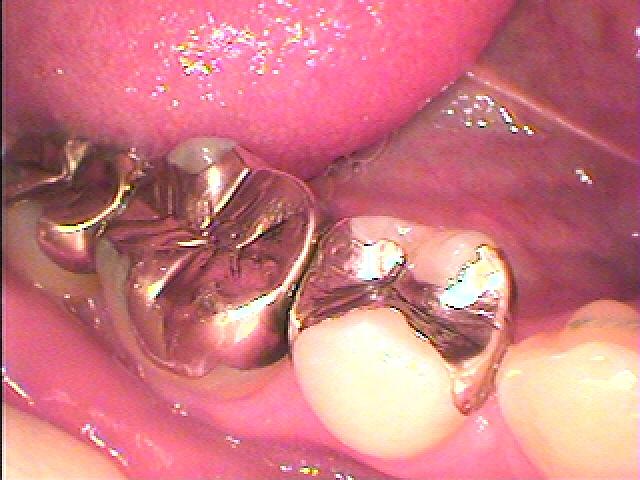

問題の歯になります

この銀歯を外していきます